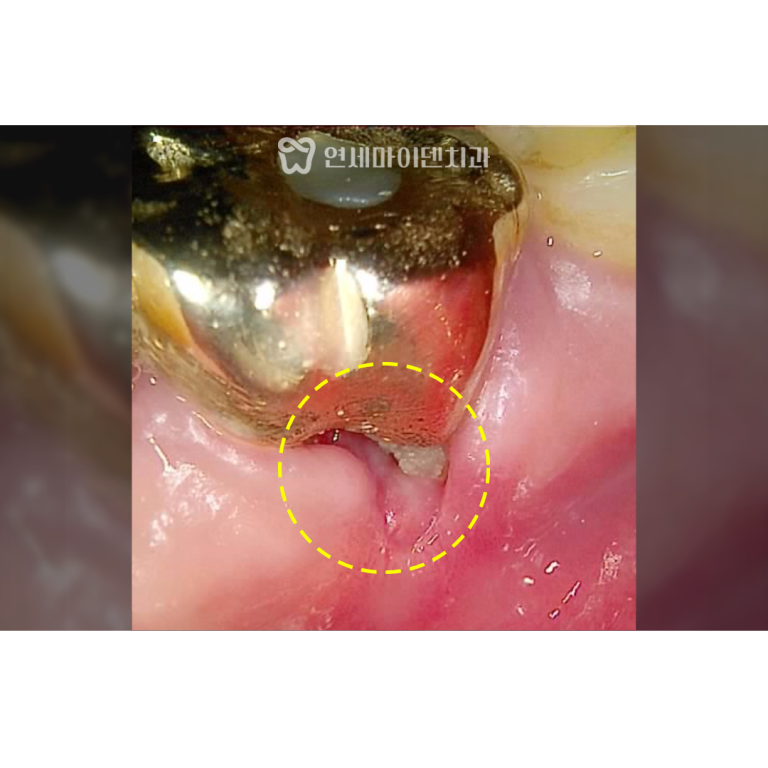

보철물을 제거하자 내부에서 출혈이 계속되어 CT를 재확인했더니

구개측 뿌리(perforation)가 뚫린 상태였습니다.

염증으로 인해 주변 뼈 손실이 심했고,

이미 MTA(특수 치근 수복재)를 적용하기엔

시기를 놓친 상태였습니다.

이 경우 선택지는 두 가지입니다.

- 뿌리 절제술로 일부 뿌리만 남기는 방법

- 발치 후 임플란트 식립

환자분과 충분히 상담한 결과,

발치 즉시 임플란트를 선택하셨습니다.